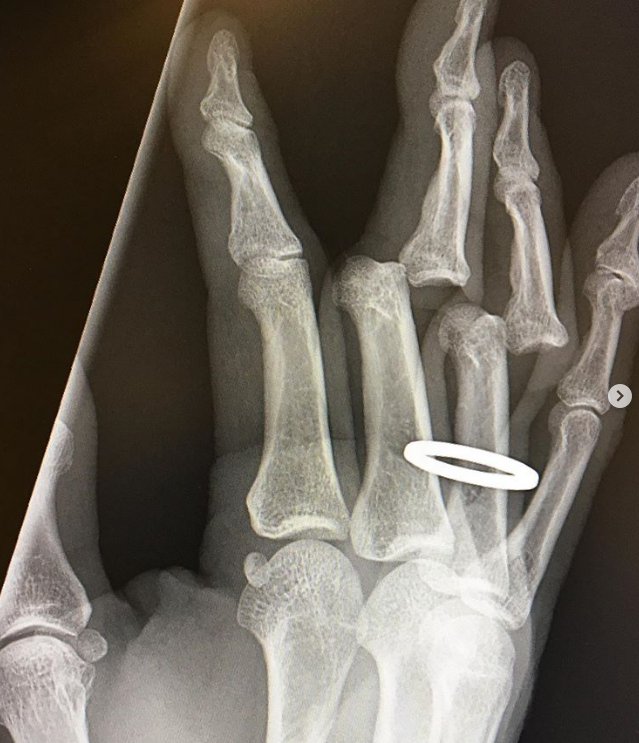

右手无名指指骨远端骨折,骨折线为y型.有点问题想咨询.

图片尺寸2592x1944